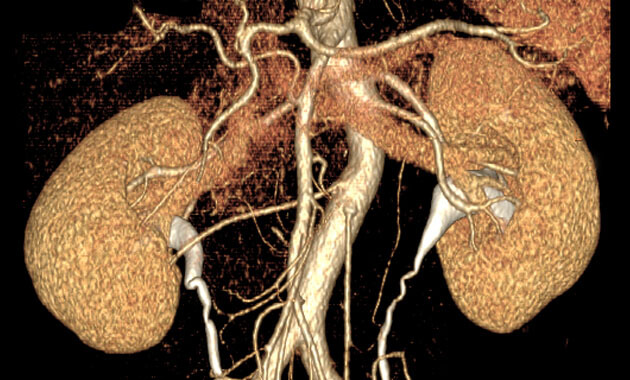

- Kidney cancer (including renal cancer)

Kidney Cancer: Why Tumor Ablation May Be a Good Treatment Choice

Kidney Cancer: Why Early Treatment is Critical